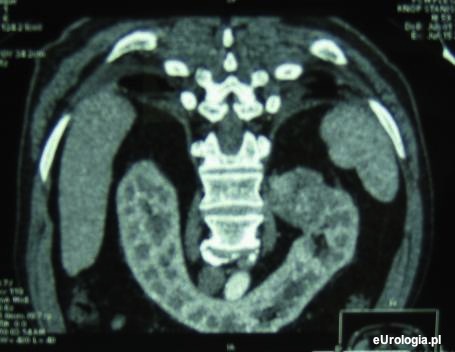

Nerka podkowiasta jest dobrze widoczna w tomografii komputerowej jamy brzusznej. O tym czy operacja guza jest możliwa powinien wypowiadać się lekarz, który zajmuje się pacjentem. Poniżej można zobaczyć jeden ze skanów tomograficznych nerki podkowiastej z guzem 5 cm górnego bieguna nerki lewej. Pacjentka została zoperowana - nefrektomia lewostronna.

Fot. Nerka podkowiasta z guzem górnego bieguna lewej nerki.